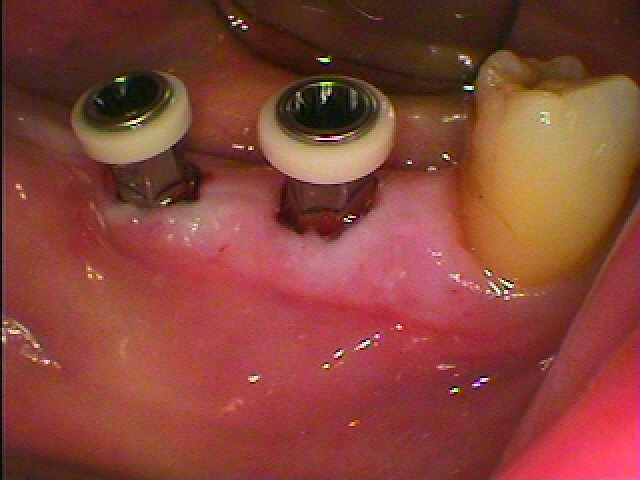

インプラント埋入時になります

ほとんど出血もありません

傷口の直りもきれいです